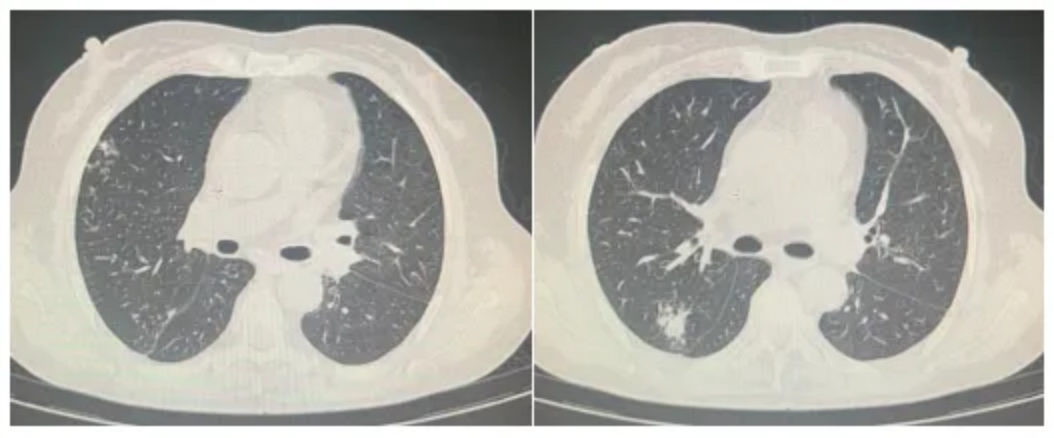

进展、复发:因疫情停药3个月后出现疾病进展。服用利妥昔单抗562.5mg+HD-MX(5.35g)+泽布替尼80mg(2次/d)后,患者再次出现头疼、恶心、呕吐,行走不稳(图4)。

图4:影像结果